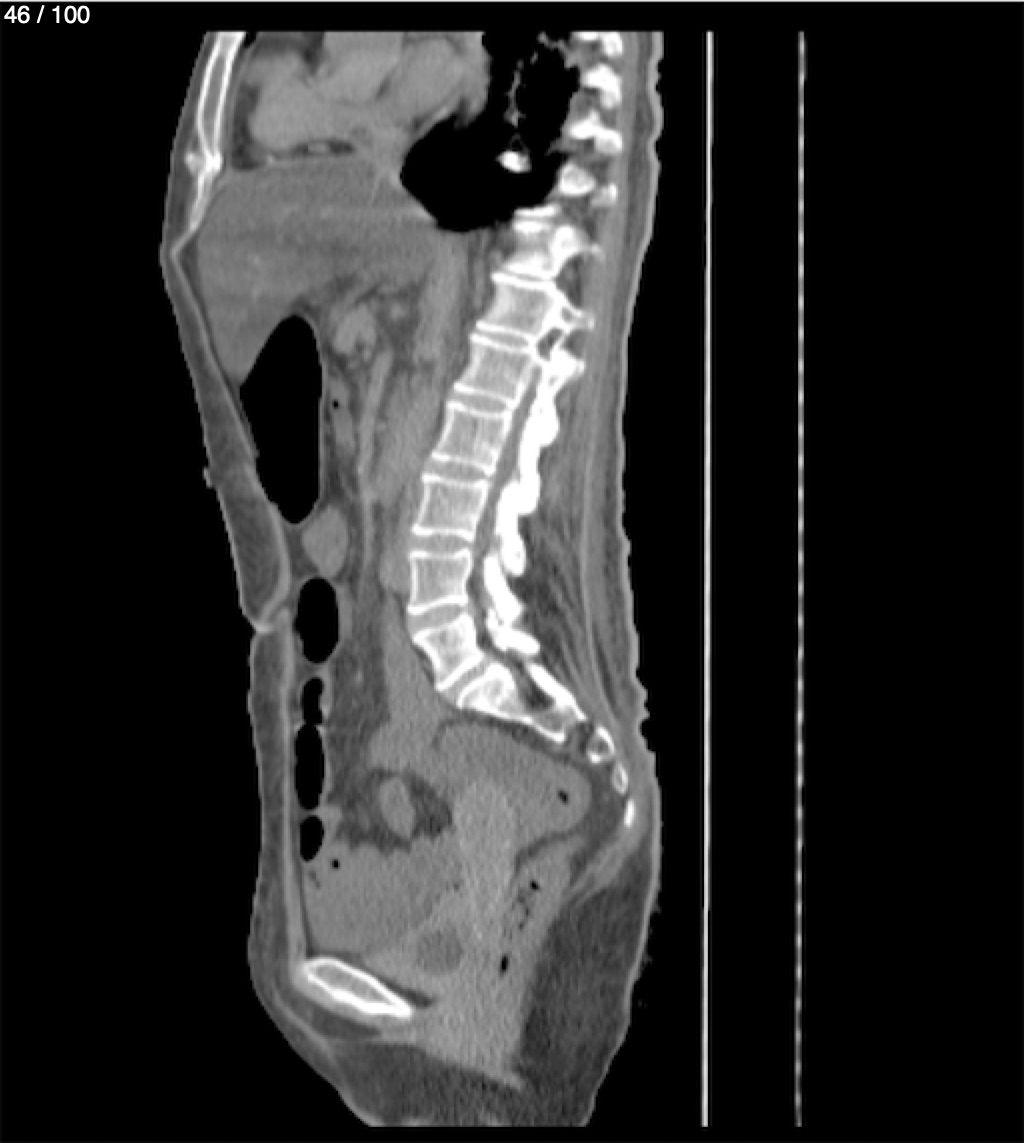

Hilda Geronimo Mendez 60A - T.C Abdomen Simple